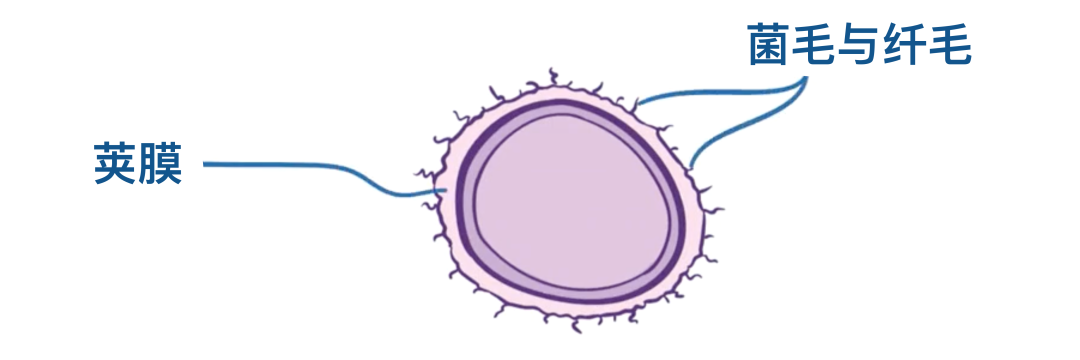

首先,肺炎链球菌有荚膜,也就是说它表面被一层多糖结构覆盖。

荚膜上有菌毛和纤毛,这些毛发样突起可以帮助细菌附着在宿主细胞上。